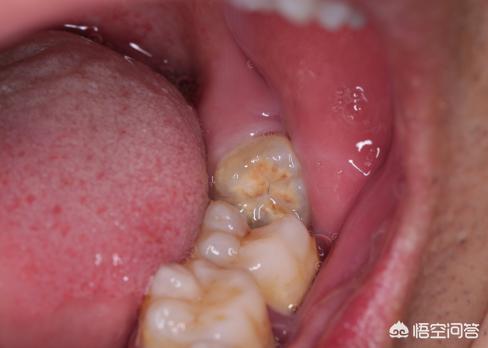

对于我们大多数人而言,智齿长的位置特殊,几乎都是萌出不全或者完全不萌出,出现各种的错位倾斜,我找了一张图,你可以对照看看你的智齿有没有如下情况,就是这些位置不正常的支持,逐渐会出现不是,导致各种问题发生。

当我们的智齿出现如上不全的状态,牙龈和牙齿之间会形成一个很深很窄的盲袋,看我找的下图你就明白了,这个盲袋容易藏匿食物残渣,而且不易清理,时间一久牙周肿胀感染,引起疼痛。当你吃东西的时候,上下牙齿一咬合咀嚼会出现摩擦,牙龈可能会被挤伤,则会出现溃疡,发炎,出现疼痛。

另外,位置不正当的智齿,容易与第二恒磨牙之间龋坏,而且这个龋坏相当隐匿,不容易发现,等你感觉的时候,可能已经是非常严重的龋坏了,因为智齿,坏了第二恒磨牙,真是可惜,如下图你看看出现的状态,不要等出现了,牙齿变化不可逆,后悔来不及。